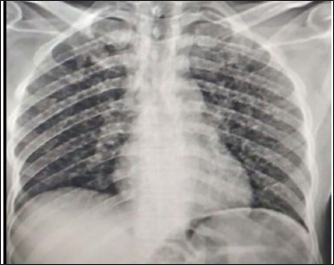

Upon investigation, chest X-ray showed multiple bilateral air space nodules (Fig. 2); abdominopelvic U/S showed numerous hypoechoic splenic lesions; complete blood count was non-remarkable; urine lipoarabinomannan (LAM) was positive, and Xpert MTB/RIF assay from the left axillary skin abscess was positive for rifampicin sensitive Mycobacterium tuberculosis (Table 1).

Fig. 2. Chest X-ray revealed multiple bilateral air space nodules.

One major differential diagnosis of cutaneous TB is scrofuloderma, which has similar clinical and histologic characteristics to metastatic tuberculous abscesses. Scrofuloderma develops as a continuous extension of an infection from an underlying tuberculous focus instead of hematogenous spread (Almagro et al., 2005). The chest X-ray findings suggestive of pulmonary TB and the absence of scrofula, were against scrofuloderma. The cutaneous manifestations in metastatic skin abscesses are most likely due to the result of hematogenous spread of Mycobacterium tuberculous bacteria.